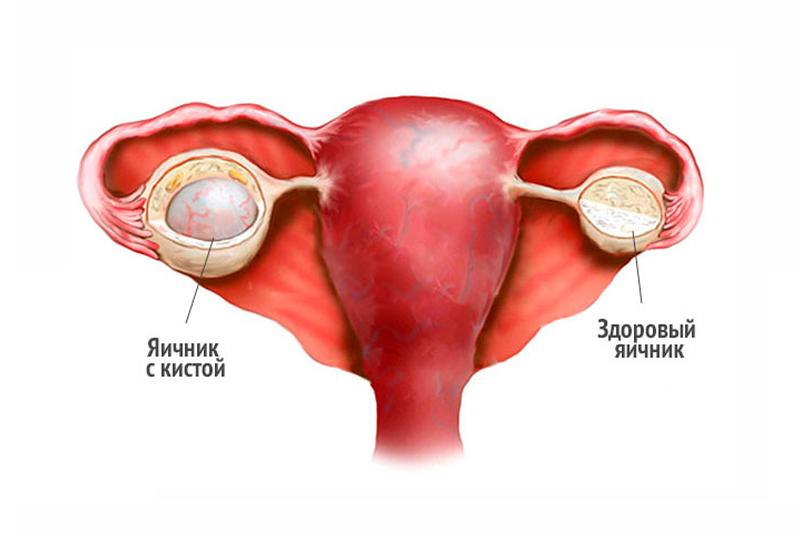

Созревание фолликула в яичнике: этапы и процессы